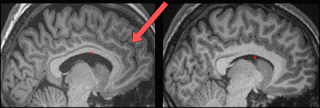

Estos autores se basaron en estudios previos que sugerían que una región de la corteza cerebral localizada en el lóbulo frontal y que se llama “corteza prefrontal anteromedial” estaba involucrada en este proceso del monitoreo de la realidad. Bueno, pues con esta evidencia fueron y buscaron si una variación morfológica de un pedacito de esa corteza –el surco paracingulado- pudiera explicar el desempeño del monitoreo de la realidad.

Sucede que estos investigadores notaron que algunos individuos no tenían surco paracingulado en su corteza prefrontal, mientras que otros individuos si presentaban este surco. Los investigadores explican esta diferencia porque al parecer este surco es de los últimos en formarse durante la gestación en el útero. Bueno, pues entonces los investigadores fueron y buscaron al banco de imágenes de cerebros de la Universidad de Cambridge y seleccionaron sujetos con y sin el surco paracingulado para analizar su desempeño en una tarea de monitoreo de la realidad. La tarea era bien sencilla. Básicamente usaron pares de palabras comunes, como “el gordo y el flaco” o “Yin y Yan”. En unas instancias ponían únicamente una de las palabras y les pedían que se imaginaran la segunda, mientras que en otras instancias les pedían que ellos leyeran el par de palabras, o que escucharan que el investigador leía el par de palabras. En la segunda fase del experimento les preguntaban si se acordaban si ellos habían visto o imaginado cierta palabra, o bien si el investigador o ellos habían leído el par de palabras.

Los resultados fueron sorprendentes. Los investigadores encontraron que aquellos individuos que no presentaban el surco paracingulado en ninguno de sus dos hemisferios cerebrales, presentaban menos aciertos en su monitoreo de la realidad que el grupo de voluntarios que tenían uno o los dos (uno en cada hemisferio) surcos paracingulados. Esto implica que una simple variación en la corteza frontal impacta el desempeño en nuestro monitoreo de la realidad. Sorprendentemente, los sujetos con un menor número de aciertos seguían estando tan confiados en sus respuestas como aquellos sujetos que tuvieron un desempeño significativamente mejor.